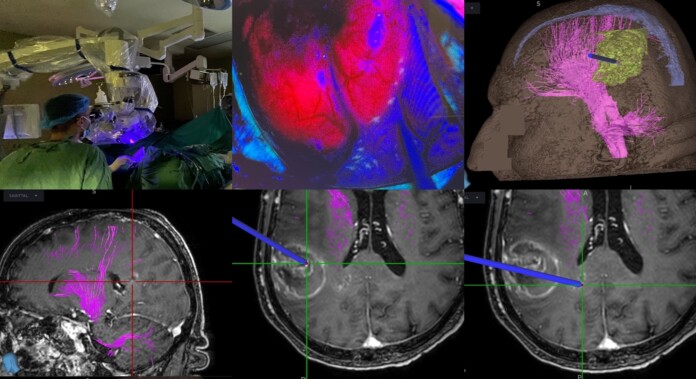

Η χρήση του 5-αμινολεβουλινικού οξέος επιτρέπει τον φθορισμό και αναγνώριση του όγκου διεγχειρητικά με τη χρήση ειδικού τύπου μικροσκοπίου που διαθέτει η Νευροχειρουργική Κλινική. Έτσι μπορεί να γίνει αναγνώριση και πιο εκτεταμένη εξαίρεση του νεοπλασματικού ιστού, κάτι που έχει αποδειχθεί ότι αυξάνει την επιβίωση σε ασθενείς με υψηλής κακοήθειας γλοιώματα εγκεφάλου.

Επιπλέον, έγινε διεγχειρητική χρήση νευροπλοηγού, που διέθετε αλγόριθμο νέας τεχνολογίας για δεσμιδογραφία, κάτι που επιτρέπει την χαρτογράφηση σημαντικών οδών του εγκεφάλου και επομένως την επιλογή της κατάλληλης χειρουργικής προσπέλασης, με σκοπό την αποφυγή μόνιμου νευρολογικού ελλείμματος μετεγχειρητικά.